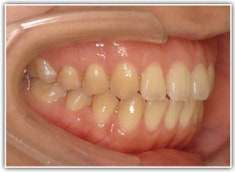

治療後(1年8ヶ月後)

かなり重度のオープンバイト症例です。骨格的な要素も強く出ております。通常であれば外科矯正適応のパターンですが、当院では矯正治療のみで、外科は行いません。

動的治療後セファロ分析

良好な咬合関係が認められます。